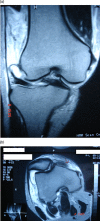

(A and B) MRI pictures of the right knee coronal and axial view demonstrating the buttonholing of the medial femoral condyle and entrapment of the medial capsuloligamentous structures in the medial joint cavity. There is mid-substance tear of the medial collateral ligament.